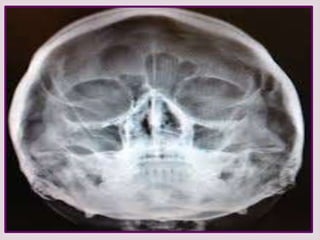

EXÁMENES RADIOGRÁFICO

RX SENOS PARANASALES

De poca ayuda en el dx de pólipos

nasales altos falsos positivos y falsos

negativos.

TUMOGRAFIA COMPUTADA TC

Para confirmar localización y

extensión de la lesión. De gran

utilidad permite planear tipo de

cirugía y evitar complicaciones .